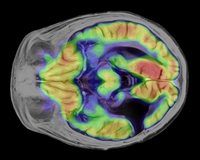

İSTANBUL – Manyetik rezonans (MR) ve pozitron emisyonu tomografisi (PET) teknolojilerini buluşturan bu yeni cihaz, ilk kez doktorlara iç organların yerlerini, nasıl çalıştıklarını ve metabolizma yapılarını aynı anda tek  görüntü içinde görme imkanı veriyor.

Bu cihaz, sadece bir tümörün vücudun hangi bölümünde olduğunu değil, aynı zamanda tümörün türü ve aktivitesini göstererek doktorların daha doğru teşhis koymalarına yardımcı oluyor. Ek olarak, cihaz sayesinde verilen ilaçlara karşı hasta vücudunun nasıl tepki verdiği de görüntülenebiliyor.

Radyofarmasötik ilaçlar, vücut dokularıyla reaksiyona giriyor ve ortaya çıkan radyasyon ölçülüp nihai olarak bir görüntü şeklinde aktarılır. Bu görüntüleme tekniklerinde uygulanan fizik kurallarına göre bu iki teknolojinin birbiriyle çelişen görüntüler üretmesi gerekir ki bu da aynı anda görüntülemeyi imkânsız kılar. Ancak Siemens Biograph mMR, bu engelin üstesinden gelecek şekilde tasarlanmıştır. Söz konusu iki teknolojinin tek sistem içinde birleştirilmesinin, çok sayıda kanser türü ve demans hastalığı dâhil olmak üzere birçok hastalığın teşhisini değiştirmesi bekleniyor.